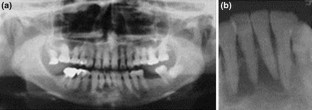

Glandular odontogenic cyst (GOC) is a rare odontogenic cyst derived from the odontogenic epithelium. GOC shows unpredictable and potentially aggressive behavior. Although enucleation and curettage are applied in most cases, the recurrence rate remains relatively high. Because a standard care procedure for GOC has not been established, we propose a new treatment procedure for GOC. In this case report, we describe a 62-year-old Japanese woman who suffered from GOC arising at the anterior region of her mandible and who was treated using the dredging method. She underwent enucleation and curettage twice using the dredging method with preservation of the teeth, which were involved with the lesion, but the lesion recurred 2 years later. In addition to enucleation and curettage, apicoectomy of the teeth was performed with a third dredging method procedure, and prognosis has been good with no recurrence for 18 months since the last treatment.

Fig. 2